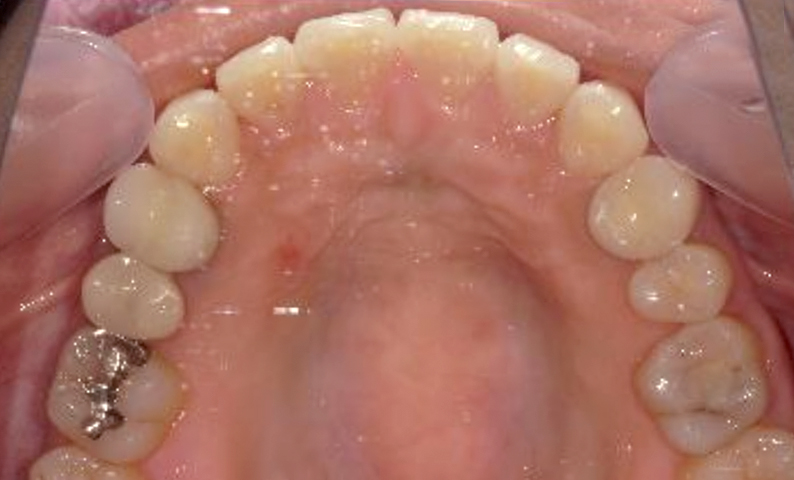

| 治療前 | 治療後 |

|---|---|

|